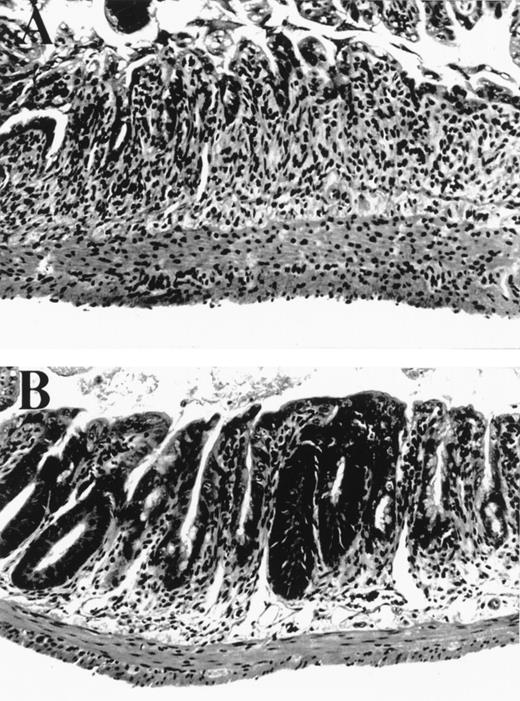

We tested the effects of KGF in a well established murine BMT system where GVHD is induced by both minor and major histocompatibility antigens (B6→ B6D2F1). We hypothesized that KGF may protect the GI tract epithelium from damage inflicted by cellular and inflammatory cytokine effectors of GVHD that occur in addition to that from radiation and chemotherapy. BMT recipients were conditioned with 1,550 cGy of TBI and transplanted with 2 × 106splenic T cells and 5 × 106 bone marrow cells from B6 (allo) or B6D2F1 (syn) mice. KGF was given to allogeneic BMT recipients from day -3 to day +5 at a dose 5 mg/kg/day subcutaneously. The severity of GI histopathology was examined on day 5 after BMT, a time of maximal GI damage in this model, according to a standard scoring system.15 Macroscopic evaluation of control-treated allogeneic recipients showed dilated and edematous bowel, while the intestine in both syngeneic and KGF-treated allogeneic mice appeared normal (data not shown). Microscopically, the small bowel in allogeneic BMT controls was more severely damaged than in syngeneic controls, with significant differences in several features of mucosal architecture and epithelial cytology (Table 1). The large majority of these parameters was reduced by KGF treatment (Table 1 and Fig 1) to the level found in syngeneic BMT recipients, completely abrogating the damage specific to GVHD. Interestingly, KGF treatment given before BMT only did not significantly protect the GI tract from GVHD (Table 1). KGF administration from day -3 to +5 also significantly reduced damage to colonic mucosa in allogeneic animals as determined by semiquantitative scoring of histologic features, which were specific for GVHD as described in Materials and Methods (KGF allo v control allo: 1.8 ± 0.5 v 9.0 ± 0.8, P < .001).

Small bowel histology 5 days after BMT. (A) Allogeneic control mouse, exhibiting severe villus blunting, extensive crypt destruction with no appreciable regenerative response, and a moderate lamina propria inflammatory infiltrate. (B) Allogeneic mouse treated with KGF from day -3 to +5 exhibiting moderate villus blunting, prominent crypt regenerative features, and minimal lamina propria inflammatory infiltrate. Features in syngeneic control mice (not shown) were identical to those in KGF allogeneic animals.

Damage to GVHD target organs is mediated by both inflammatory cytokines (IL-1, TNFα, IFNγ) and cellular effectors (CTL and NK cells).23 Injury to the GI tract is mediated predominantly by TNFα, while the Fas-dependent CTL pathway is important in the development of hepatic GVHD.24 GVHD histopathology in the GI tract has been described in three phases,25 and we have included discriminatory parameters from each phase in our histological scoring system. The initial proliferative phase results in increased crypt cell mitotic activity, crypt lengthening, and increased intraepithelial lymphocytes. However, the histological features of GI tract GVHD in this model are consistent with the destructive and atrophic phases, characterized by villus blunting, lamina propria inflammation, crypt destruction (with crypt stem cell loss), and mucosal atrophy (Table 1). These features together with epithelial vacuolization and attenuation are induced by inflammatory cytokines such as TNFα26 and IL-1.27 The dramatic amelioration of these histological features in KGF-treated recipients is therefore consistent with the reduction in serum TNFα levels in these animals. Disruption of the GI mucosal barrier facilitates the translocation of LPS, a normal constituent of endogenous bowel flora, into the systemic circulation.4 LPS is a potent stimulus for inflammatory cytokine production18 and augments donor T-cell activation,28 thereby amplifying both inflammatory and cellular effectors of GVHD. In this study, KGF administration inhibits TNFα generation, most likely by protecting the GI epithelium from GVHD injury, which is mediated by both TBI and alloreactive T cells.4 Disruption of LPS leakage suppresses TNFα generation that mediates ongoing gut injury4 and thus the “indirect” blockade of inflammatory cytokines by KGF provides dramatic protection from GVHD.